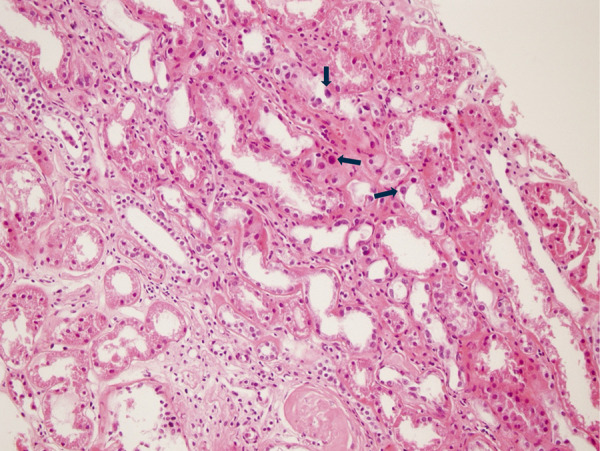

Karyomegalic interstitial nephritis (KIN) is a rare hereditary form of chronic interstitial nephritis that was first described over 50 years ago. It is characterized by karyomegalic tubular epithelial cells and progressive chronic kidney disease, often leading to end-stage renal disease by the fifth decade of life. Recent studies have identified FAN1 mutations as a key genetic contributor, with additional associations to environmental factors and toxic exposures, such as ochratoxin A, alkylating agents, and heavy metals, which may act as potential triggers of the disease. We present a detailed analysis of KIN cases, highlighting genetic diversity, clinical manifestations, and management challenges, complemented by a comprehensive review of the literature.

Abstract Image